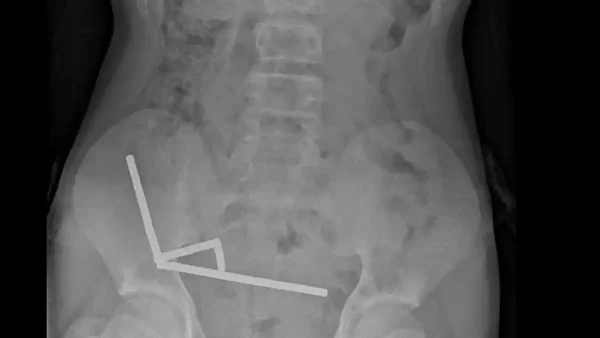

Ο 13χρονος παραδέχτηκε ότι είχε καταπιεί περίπου 80-100 ισχυρούς μαγνήτες - Πήγε στο νοσοκομείο μετά από 4 ημέρες έντονου πόνου στην κοιλιά